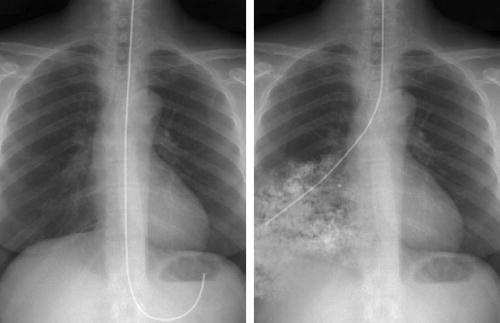

CORRECT NG PLACEMENT

INCORRECT NG PLACEMENT